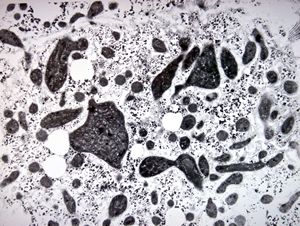

M,16y. | lipofuscin - hyperbilirubinaemia - Gilbert or Dubin-Johnson syndrome

M,17y. | lipofuscin - hyperbilirubinaemia - Gilbert or Dubin-Johnson syndrome

M,17y. | hyperbilirubinaemia - lipofuscin - Gilbert or Dubin-Johnson syndrome

F,12y. | lipofuscin - hyperbilirubinaemia - Gilbert or Dubin-Johnson syndrome